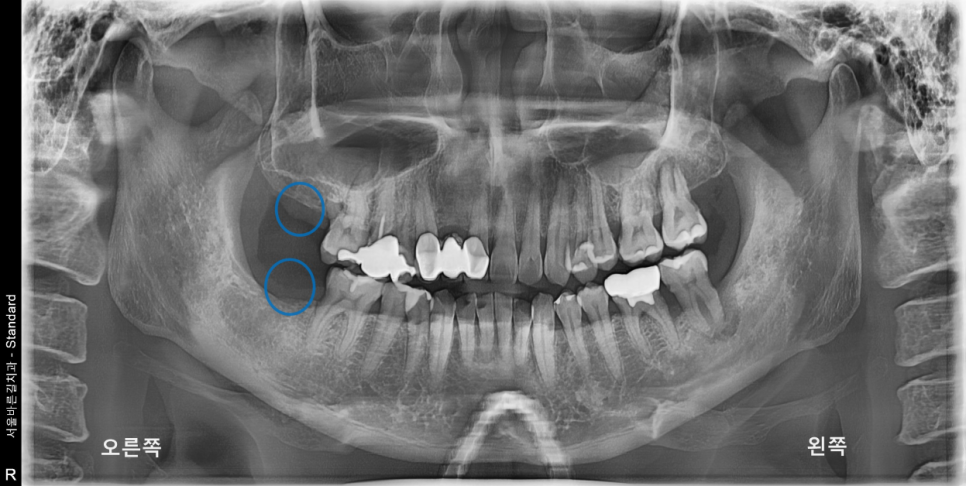

제가 그림에 표시해둔 곳을 보면 처음 내원하셨을 때부터,

오른쪽 위, 아래 가장 끝 치아도 같은 이유로 결손 된 상태로 지내고 계셨습니다.

물론 완벽한 구강상태를 위해서는 임플란트 식립까지 필요한 상태였지만

본원에서는 환자분의 개개인의 니즈에 당연히 맞춰야 한다고

생각하기에 발치까지만 진행하였습니다.